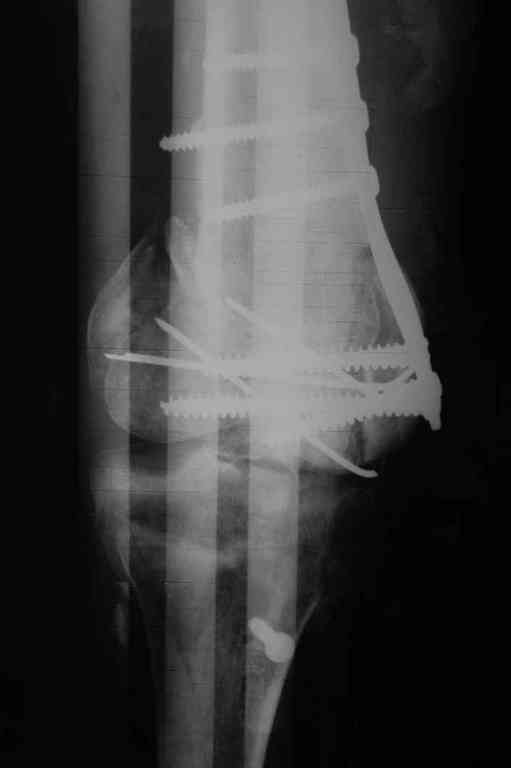

Здесь применение материала Plexur http://www.plexur.com для пластики при дефектах кости у больной с огнестрельной раной латерального тибиал плато с повреждением малоберцового нерва. Несмотря на интактный медиальный мышелок, для профилактики от вальгуса установлен АВФ и сделана ангиограмма.

После нескольких обработок и вакуумирования, поэтапно сделана фиксация тибиального бугра шурупами. И окончательную фиксацию закончили латеральной пластиной для тибиал плато и установкой пластического материала.

Для закрытия мягкотканых дефектов привлечена другая служба.